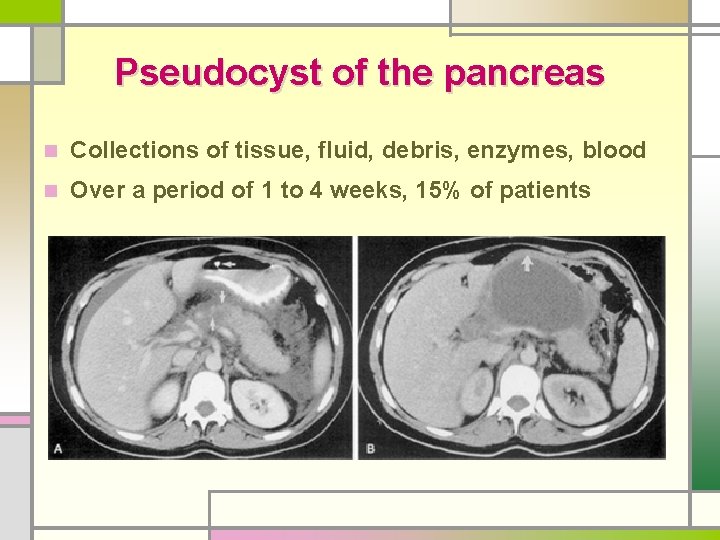

Pseudocyst of the pancreas n Collections of tissue, fluid, debris, enzymes, blood n Over a period of 1 to 4 weeks, 15% of patients

n No epithelial lining n Commonly disrupted pancreatic ductal system n Body or tail area >> head n Serum amylase: elevated in 75%, may fluctuate n Treatment - more than 5 cm in diameter, > 6 weeks - expectant management: best course in selected Pt - size is not an absolute indication for therapy Acute Pancreatitis